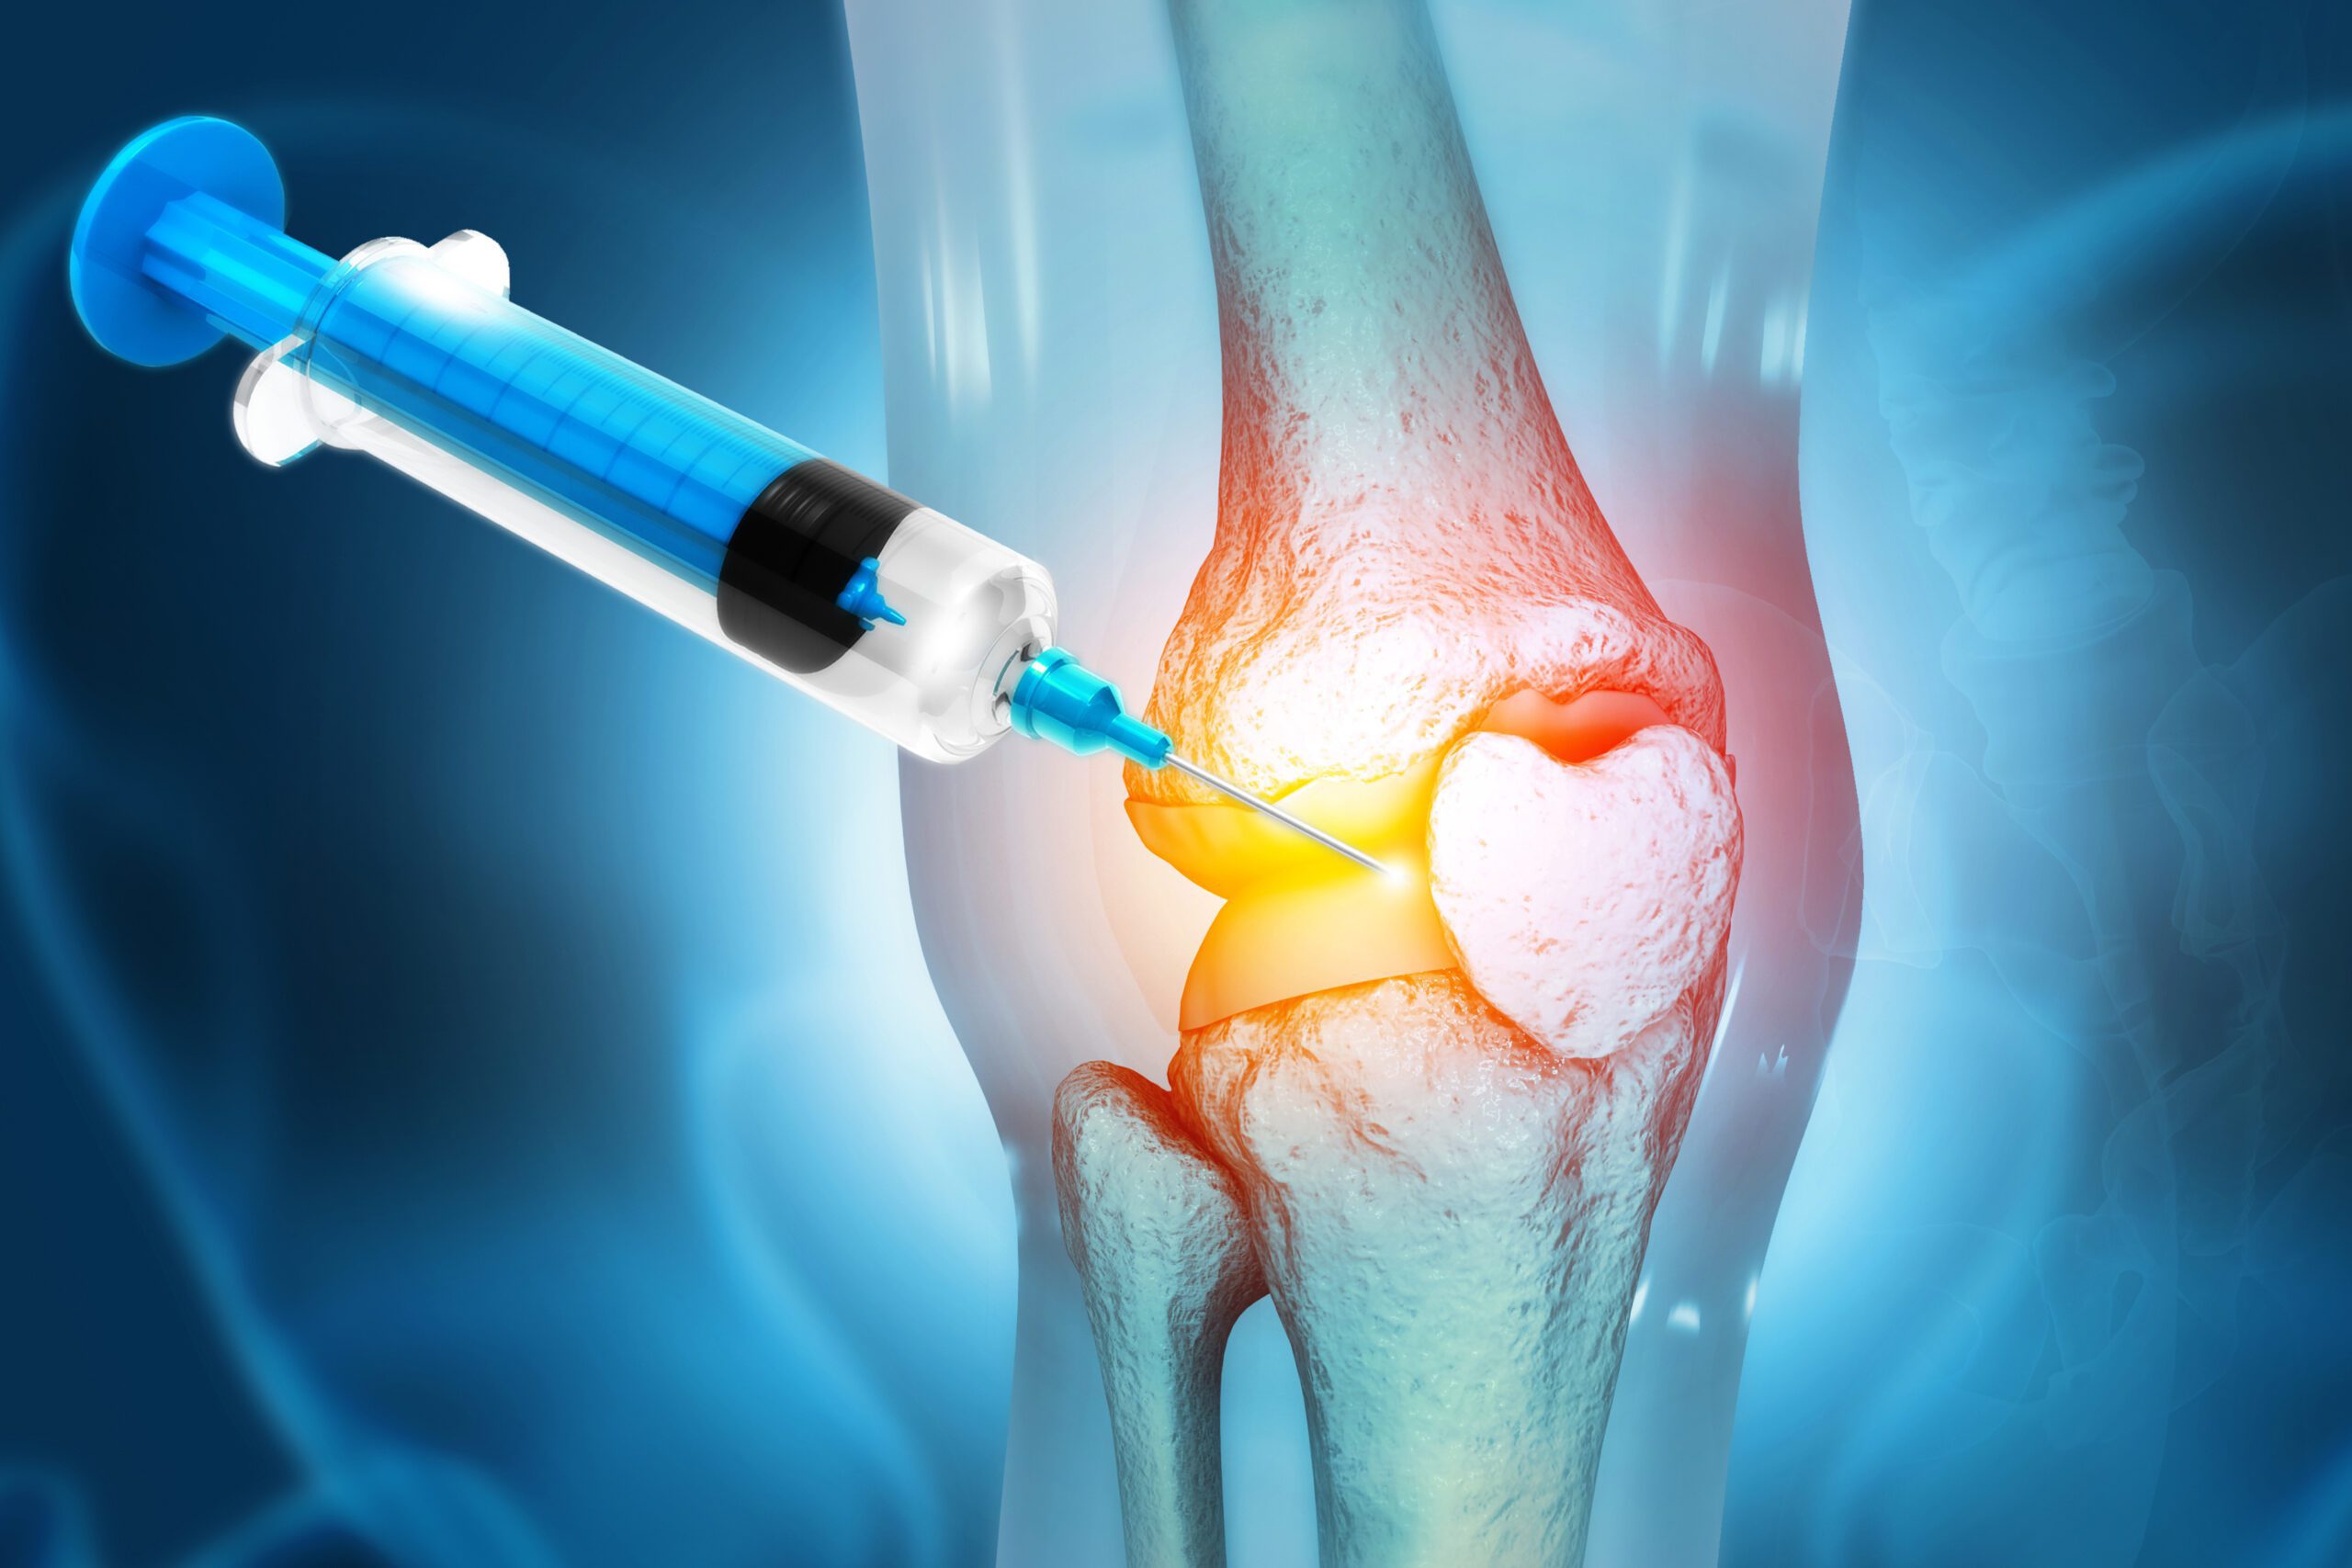

استفاده از پلاسمای غنی از پلاکت (PRP) یکی از درمان های نوین برای ارتروز زانو است. اینجا برخی از مهمترین موارد درباره درمان ارتروز زانو با پلاسما را توضیح میدهم:

– پلاسمای غنی از پلاکت حاوی فاکتورهای رشد و سیتوکین هایی است که میتواند التهاب را کاهش داده و روند ترمیم و بازسازی بافت را تسریع کند.

– ابتدا خون بیمار گرفته میشود و سپس با استفاده از سانتریفیوژ، پلاسمای غنی از پلاکت استخراج میگردد.

– پلاسمای غنی از پلاکت سپس به مستقیم به داخل مفصل زانو تزریق میشود.